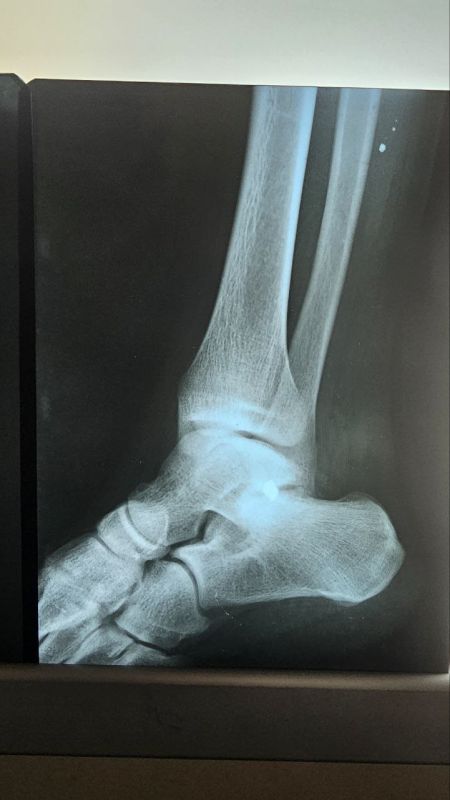

Донецкие врачи удалили подростку объемную опухоль кости14-летний подросток поступил в Республиканский травматологический центр (РТЦ) Минздрава ДНР с диагнозом «остеохондрома большеберцовой кости».Опухоль выдавила малоберцовую кость и разорвала...